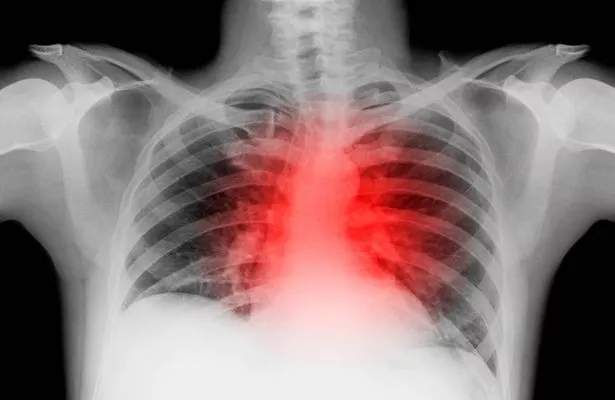

该团队特别热衷于了解这些模式如何影响心血管健康和疾病风险。英国心脏基金会的数据显示,仅在英国,心脏病和循环系统疾病就占所有死亡人数的四分之一。

有趣的是,结果显示,晚上吃得晚的男性患心血管疾病的风险比不吃的男性高55%。与此同时,不吃早餐的男性患心血管疾病的风险也比那些优先吃早餐的男性高27%。

哈佛大学的科学家发现,晚上吃得很晚的男性患心血管疾病的风险比不吃的男性高55%(图片:盖蒂图片社)